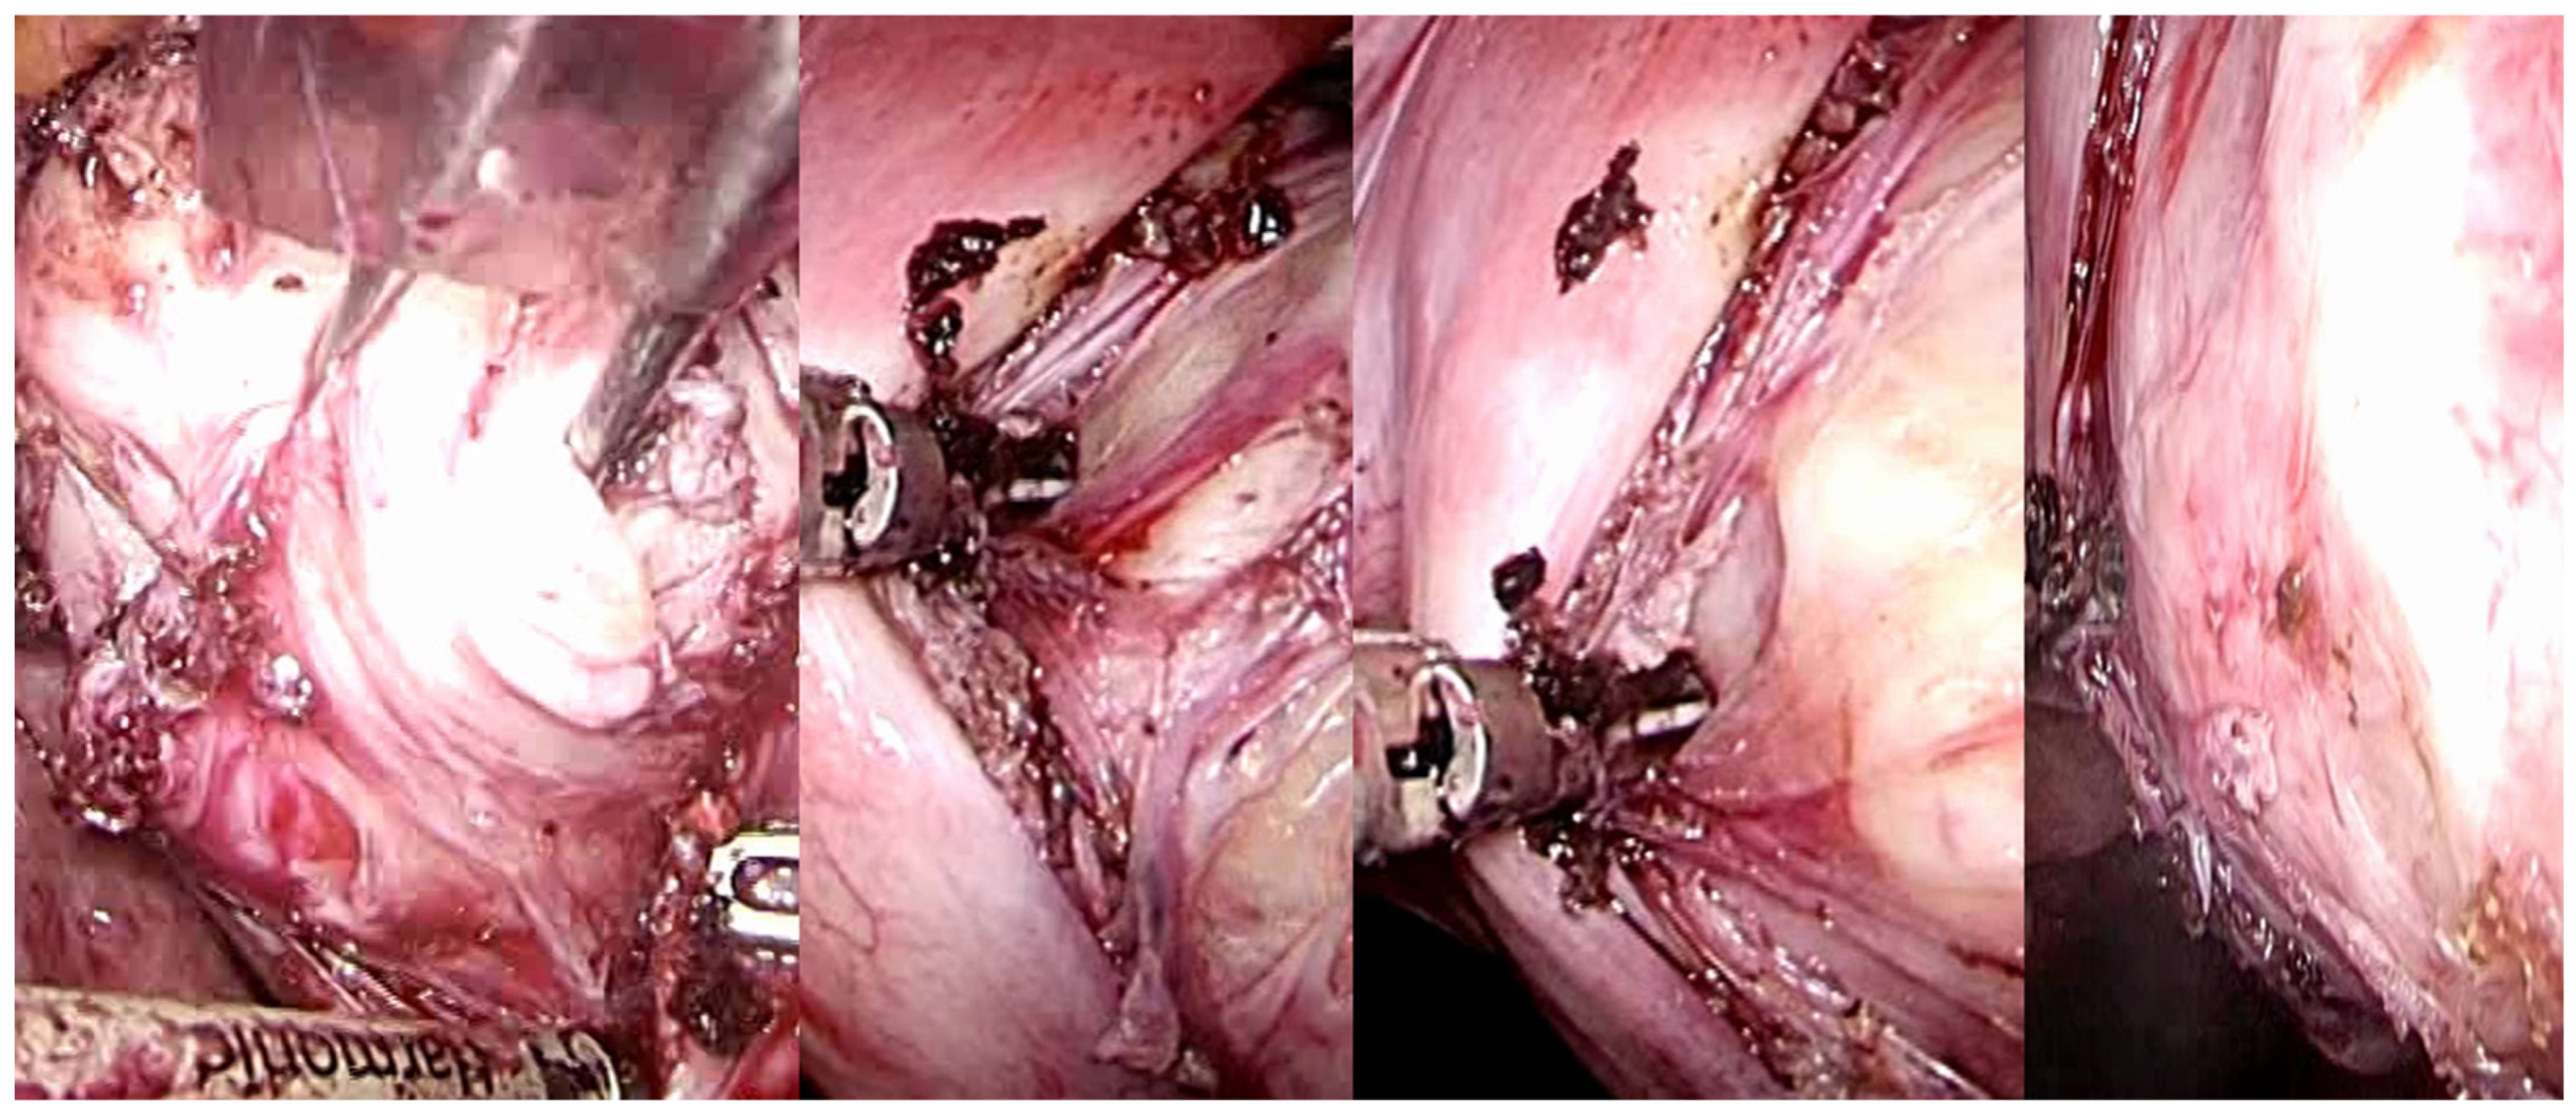

Thus, the intracapsular myomectomy procedure is predicated upon the principles of muscular physiology while concurrently adhering to anatomical considerations. By selectively coagulating the fibroneurovascular bundles of the network surrounding the fibroid, the proper application of the surgical method to biology invariably reduces blood loss during intracapsular myomectomy. Following the incision of the uterine serous surface, one continues deep until they reach the fibroid pseudocapsule, which coagulates and is cut to hook the fibroid and gently drag it outwards while coagulating and dissecting the pseudocapsule’s fibroid neurovascular bundles (Figure 7).

Figure 7.

Laparoscopic image of intracapsular myomectomy. From left, progressive identification of myoma pseudocapsule branches covering fibroid and their subsequent incision to detach and enucleate the fibroid from the pseudocapsule, with better preservation of the myometrium and neurovascular bundle.

Due to the fibroid being vascularized solely through the pseudocapsule’s veins, there can be very little bleeding before and after surgery. The objective remains the selective coagulation of the fibroneurovascular bundles during myomectomy, which allows for the reduction of bleeding to a minimum.

The proper intracapsular myomectomy approach, which selectively coagulates the pseudocapsule vessels, is undoubtedly responsible for the decreased intraoperative blood loss rather than the use of vasopressin or uterine artery occlusion [].